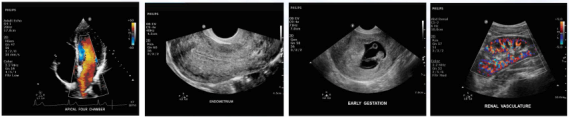

飛利浦ClearVue550/650彩超產(chǎn)品說明: